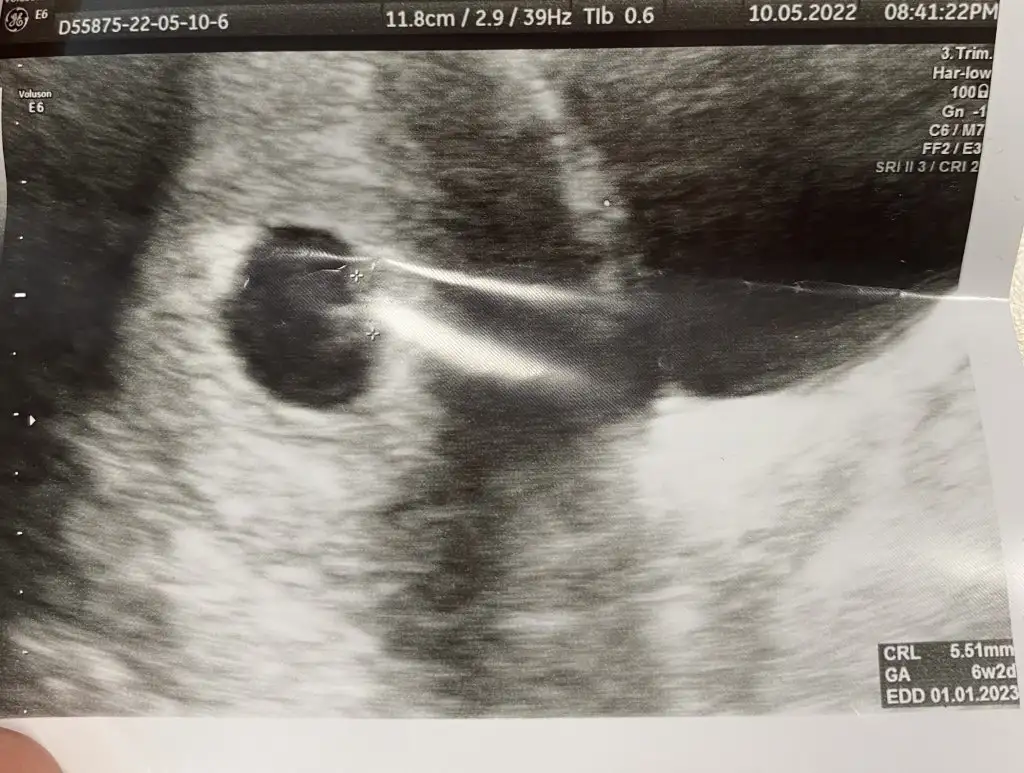

Ay kusura bakma bir öncekinde yazdım ya kafam uçmuş. 6+3 karından. Tekrar ekliyorum fotoyukızlar ah bi de kaç haftalık ve karından mı bakıldığını yazsanız

Teşekkür ederim 6+1 karından var hatta atmıştım prenses gibi demiştiniz tekrar atayım :)paşa gibi 7 haftalık görüntüsü var mı?

Karışıklık olmasın diye tekrar atayım, ilk görüntü 6+1 pazar günü olan, 2. Görüntü 6+3 salı günü olan ikisi de karından;bu görüntü 7-8 haftalık civarı mıpazar attığın görüntü peki?

seninki prenses canımKarışıklık olmasın diye tekrar atayım, ilk görüntü 6+1 pazar günü olan, 2. Görüntü 6+3 salı günü olan ikisi de karından;